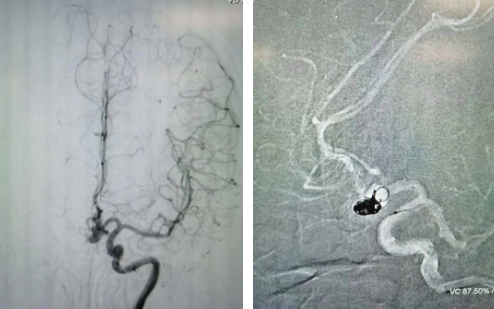

經(jīng)過全面仔細評估,西安國際醫(yī)學中心醫(yī)院神經(jīng)外科陸丹醫(yī)生決定采用微創(chuàng)介入進行治療。在取得患者及家屬同意后,3月11日,陸丹醫(yī)生為患者行Atlas支架輔助顱內(nèi)動脈瘤栓塞術。

腦血管較外周血管更為脆弱、迂曲,對術者的操作技術及精準性要求特別高。術中,陸丹醫(yī)生通過股動脈穿刺、置入微導管,再通過微導管將彈簧圏送入動脈瘤腔內(nèi),利用彈簧圈的機械閉塞作用,達到防止動脈瘤破裂的目的。術后,患者各項生命體征平穩(wěn)。

陸丹醫(yī)生介紹,此次腦科醫(yī)院首次采用Atlas支架輔助進行顱內(nèi)動脈瘤栓塞術。以往動脈瘤栓塞術中的支架輸送導管較粗,支架順應性差,易使載瘤動脈移位,而Atlas支架的輸送導管很細,輸送順滑,同時順應性及貼壁性強,能夠適應迂曲的腦遠端血管。